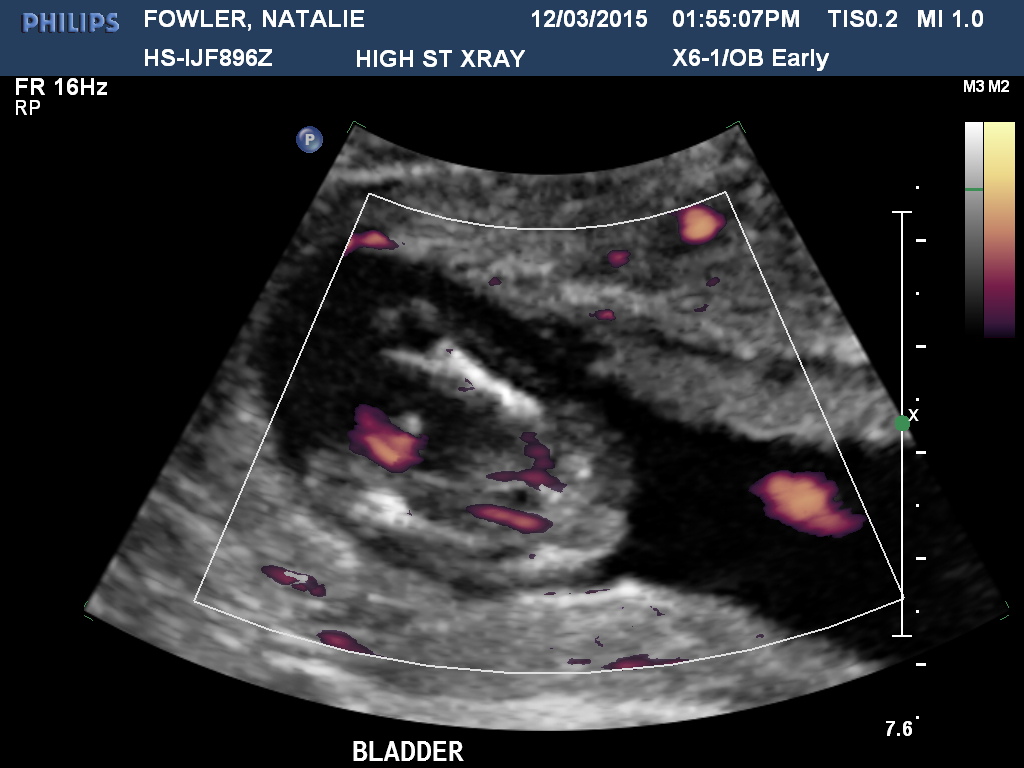

The longer I look at this scan, the more confused I get! Baby is measuring at 13w6d, any ideas would be amazing :)

youve got a lot of cord going on but id give it a boy lean

It's a tricky one. I had a nub just like that (confirmed girl) in one of my shots and it looks boy at first but because of how the baby is almost sitting upright it's just a weird angle so I'm guessing girl